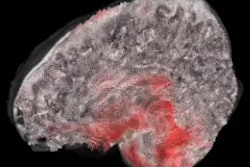

Illustration shows complexity of the data obtained from a single patient with moderate/severe traumatic brain injury. Different imaging approaches and techniques have their own unique sensitivity in assessing different aspects of neuroanatomy and neuropathology. What can be seen on images also changes with time since injury. Image courtesy of Olsen et al, Brain Imaging and Behavior, 2020.The global burden of mortality and morbidity caused by traumatic brain injury is significant. However, the heterogeneity of these patients and the relatively small sample sizes of most neuroimaging studies present a challenge for scientific advances and clinical translation, according to the group.